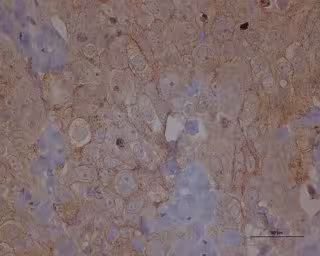

Archivo - Metástasis cáncer de ovario

Archivo - Metástasis cáncer de ovario - IDIBELL-ICO - Archivo